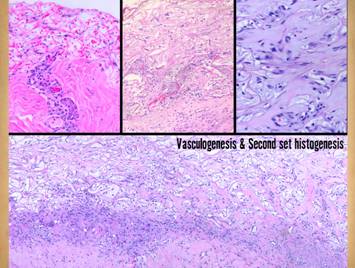

Right, five images demonstrate absence and suppression of inflammation, from patients having lower extremity dermatofasciectomy for primary lymphedema (Milroy’s, praecox).  Top left, biopsy at 4 hours after fasciectomy, just prior to placing Integra.  Normal post-traumatic thrombosis has recognized the injury, attracting polymorphonuclear leukocytes (neutrophils) which are densely marginated in blood vessels on the wound surface.  This is the normal response to injury, the start of inflammation.  Top right, biopsy 4 hours later after placing Integra.  A blood vessel is present at the wound surface between Integra matrix (top and left) and normal adipose (bottom and right).  Leukocyte margination and migration are present, but not dense.  Middle left, at 24 hours the only neutrophils are a few, in proportion to the red cells that bled into the matrix.  [First three images are from one patient, the following two are from a different patient with the same history and surgery.]  Middle right, at 5 days, the only cells present are early histogenetic pioneer and transitional cells.  There are no neutrophils, no lymphocytes, no plasma cells, no eosinophils, no monocyte-macrophages.  Other than some late foreign body giant cells occurring along the silicone interface, at no time does a defensive response ever appear in the matrix.  Bottom, at 11 days, the matrix remains mostly devoid of cells in this locale.  There is still no adverse recognition or defensive response.

At least three characteristics of Integra collagen-gag matrix explain its ability to suppress inflammation and render the wound safe from  inflammation and pathergy.  (1) Matrix chemistry prevents platelets from seeing collagen, thereby preventing the thrombotic cascade to inflammation from being triggered.  (2) The silicone artificial epidermis sequesters the wound from ambient exposure, desiccation, bioburden, and their injurious effects.  (3) The chondroitin in the matrix looks sufficiently like normal tissue that blood borne leukocytes and lymphoid cells that might find their way into the matrix do not recognize anything abnormal that would trigger a defensive response, whereas histoprogenitor cells recognize the matrix as a place to start forming new tissue.

34

Regardless what recognizes the matrix and triggers the response, once the response is initiated, the process is easy to track histologically.  It begins with small round cells which pepper the matrix.  These early “pioneer cells” have characteristics that suggest they are pluripotent stem cells, presumably derived from bone marrow.  Since the Integra matrix is insoluble and cannot issue any chemotactic signals, the discovery of the matrix by these cells is presumably a random happenstance that occurs while they are “on patrol” in the host tissue.  Once the matrix has been found, these cells bind to the matrix.  This recognition and binding is presumably a function of the aminoglycans in the matrix, since similar events are not seen on pure collagen matrices.  Once bound, these cells go into “transition”.  The transitional cells start to enlarge, cytoplasm and nuclei both getting larger in preparation for histogenic activities.